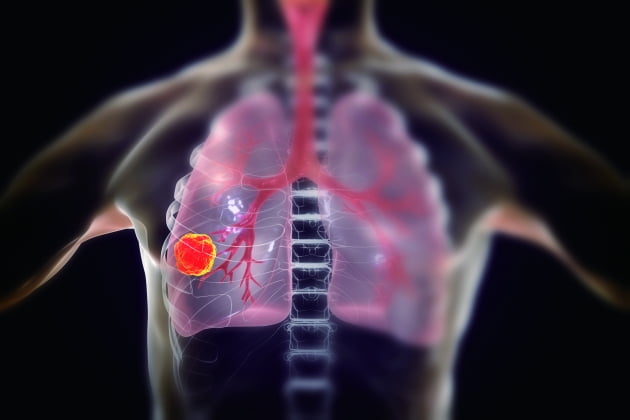

폐암 원인

흡연은 폐암의 주요 원인으로 폐암 발생의 약 85%를 차지합니다. 폐암 발병 위험은 흡연한 담배의 개수와 흡연 기간에 따라 달라집니다. 담배를 끊은 사람은 폐암 발병 위험이 낮아지지만, 과거 흡연자는 담배를 피운 적이 없는 사람에 비해 위험이 계속 증가합니다.

흡연 외에도 대기 오염, 마리화나 사용, 담배 연기 및 간접흡연, 난방을 위한 화기 사용으로 인해 석면, 방사선, 라돈, 비소, 크롬산염 등 폐암의 알려진 위험 요인에 노출될 수 있습니다. 폐암, 특히 선암과 기관지 폐포 세포암은 결핵과 같은 다른 폐 질환으로 인한 폐의 흉터로 인해 발생하는 경우도 적지 않습니다.